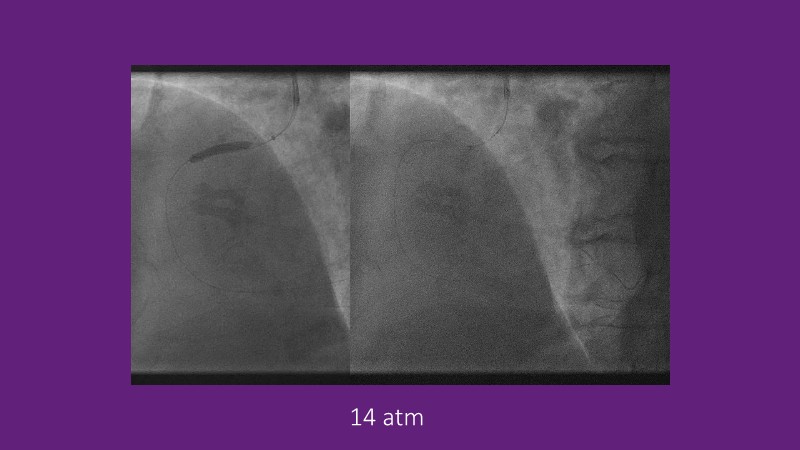

Leave nothing behind - Advancing DCB strategies in complex interventions

Explore cutting-edge strategies for optimizing drug-coated balloon (DCB) procedures in this session. Uncover practical tips to improve outcomes, review key indications, and examine international consensus on DCB use. Case presentations and expert discussions offer insights to refine your approach.